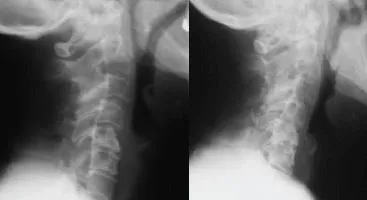

Severe Neck Degeneration & Misalignment

Ella had severe neck pain and stiffness. When the pain started traveling down her right arm, causing weakness in her hand, she became unable to work or be physically active. She had been taking pain medication for years, but the weakness...